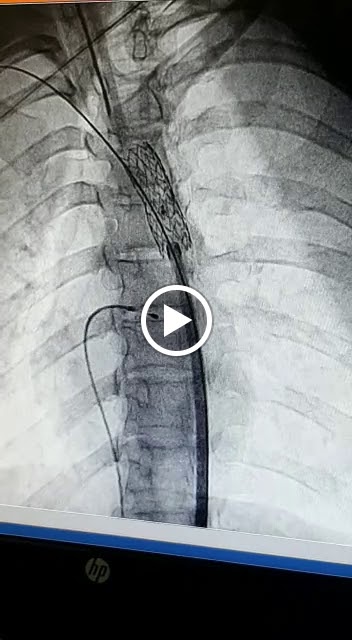

Best doctor, fully experienced in 2D echo, angiography and device closure techniques. Visited hospital and doctor for my wifes ASD problem. Angiography was done by Dr. Lalit Lawankar Sir. After angiography they suggested us to go through open heart surgery and we did it. Now everything is fine. Thanks to dr. Lalit lawankar sir for showing us correct path on correct time.